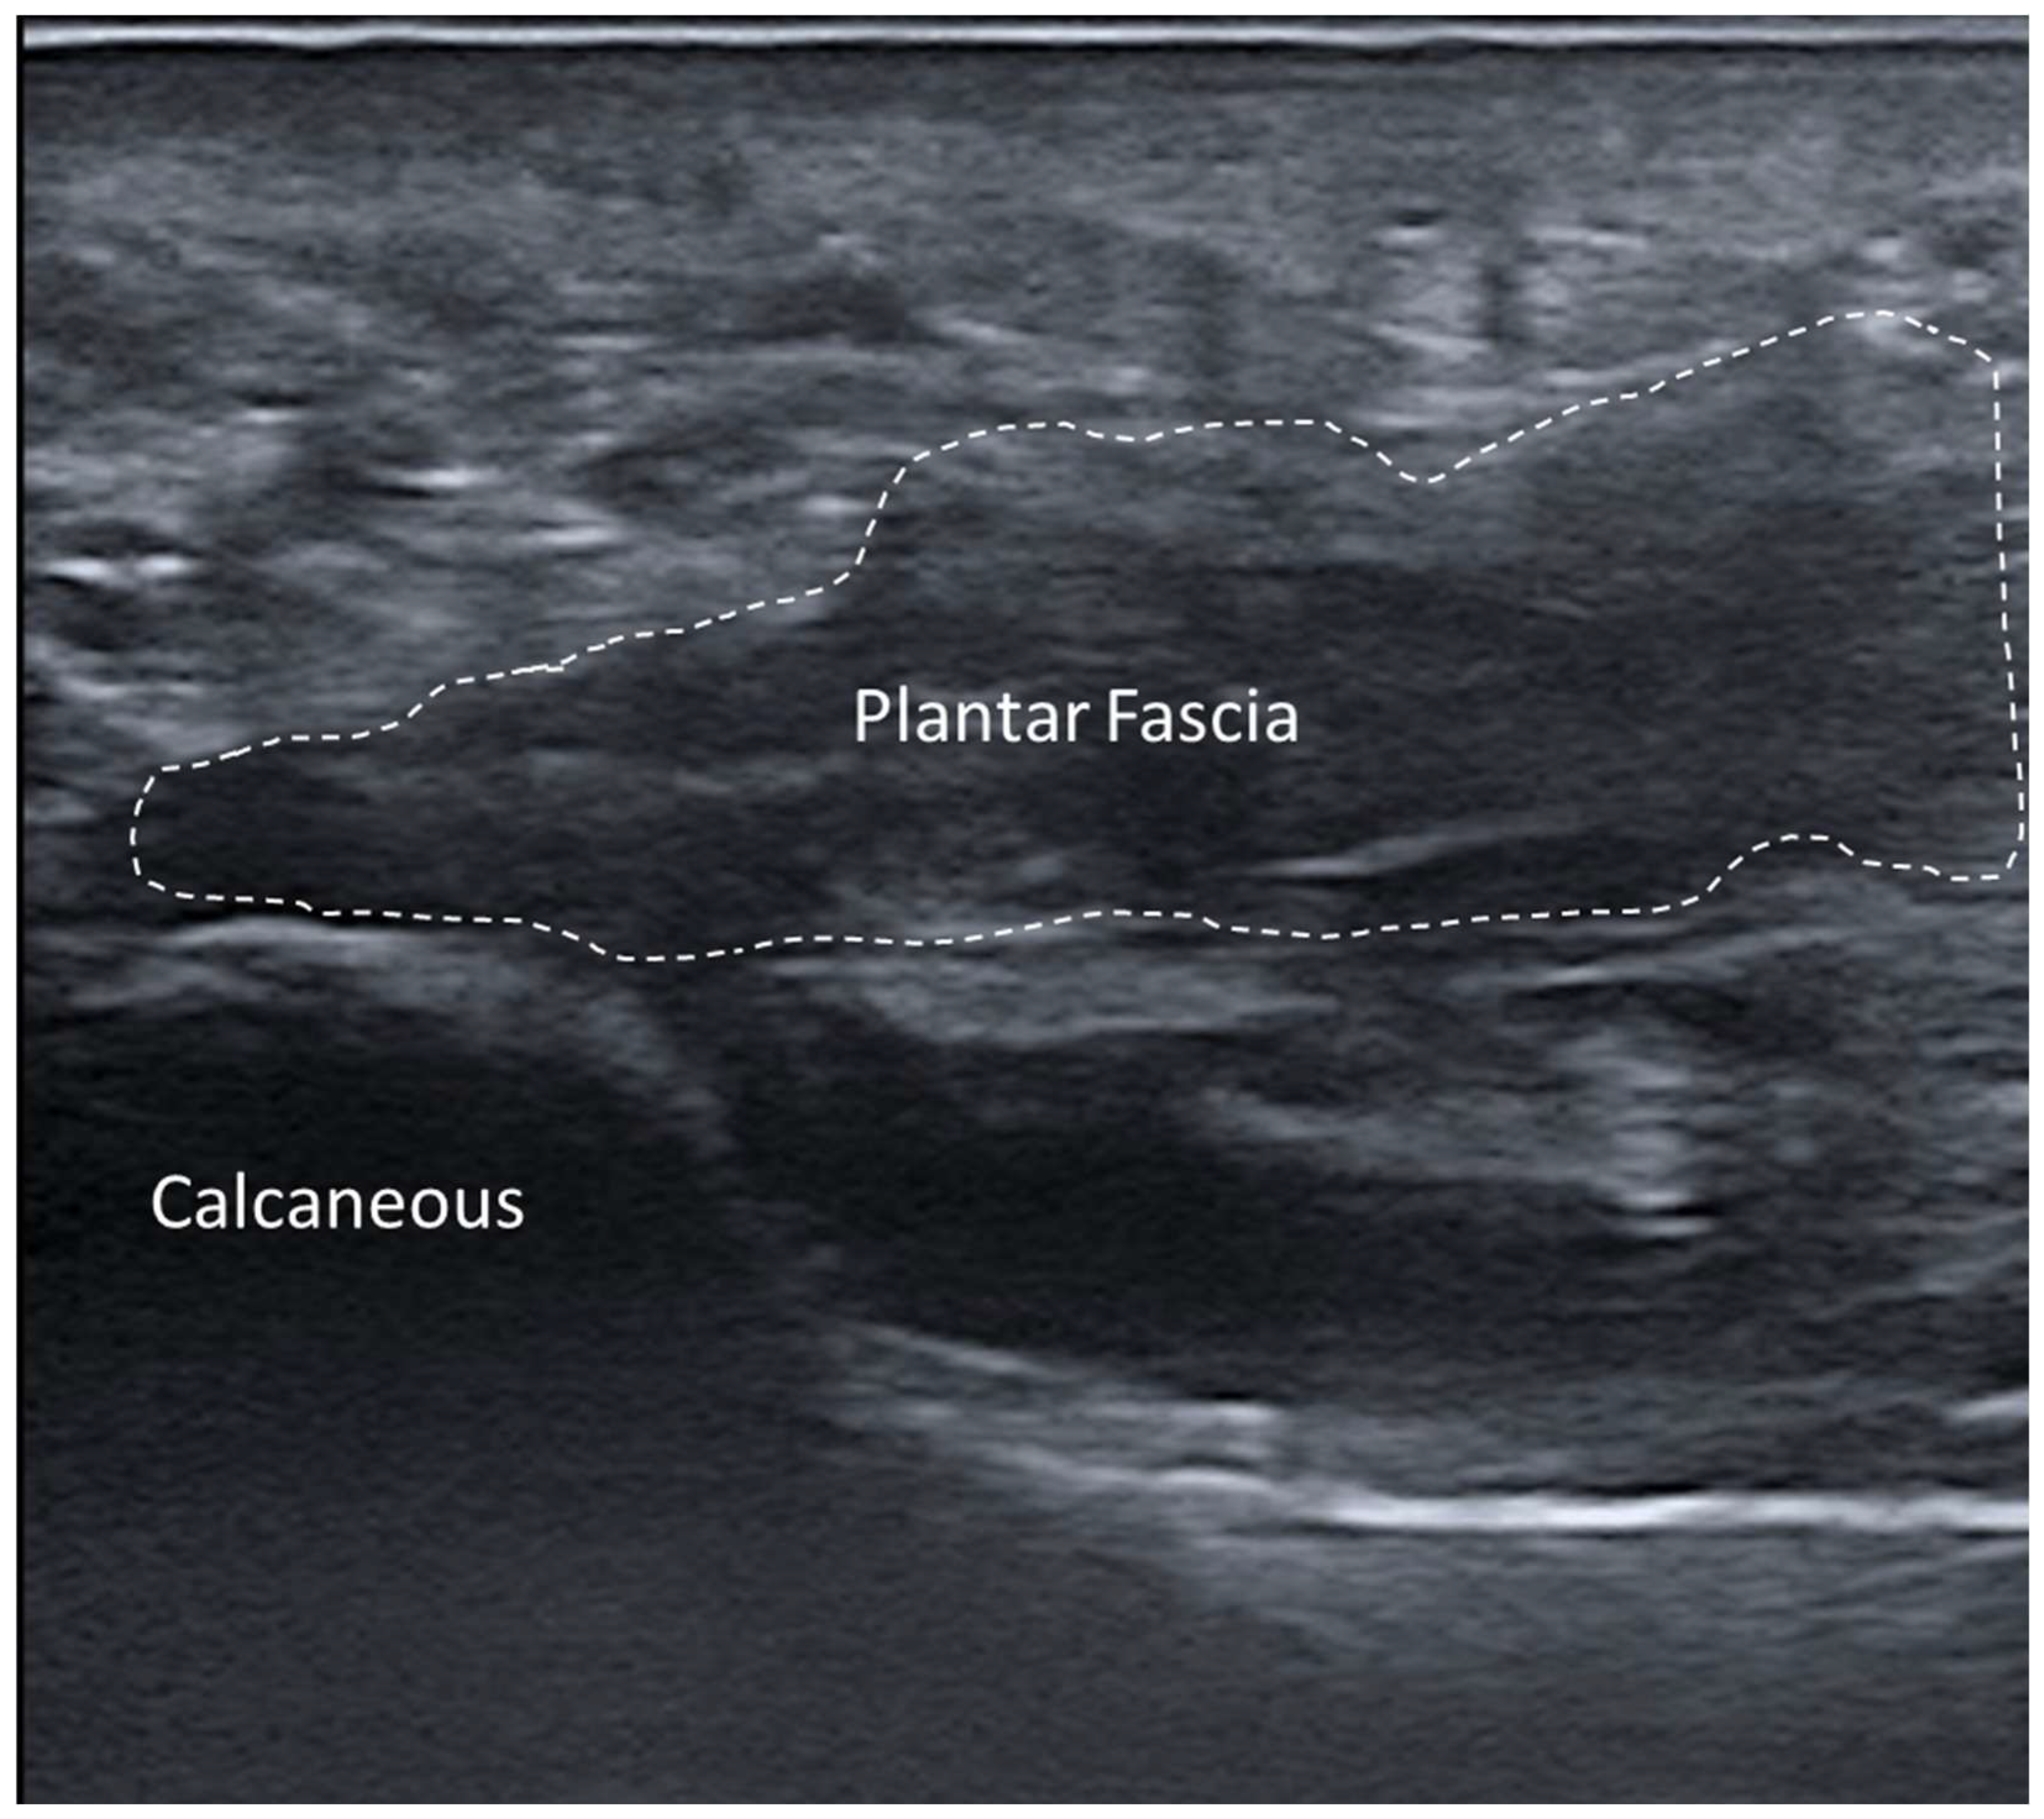

3.5.6. Plantar Fascial Rupture

- Thanwisate, T.; Siriwanarangsun, P.; Piyaselakul, S.; Tharmviboonsri, T.; Chuckpaiwong, B. Plantar Fascia Thickness and Stiffness in Healthy Individuals vs. Patients With Plantar Fasciitis. Foot Ankle Int. 2024, 45, 10711007241274765. [Google Scholar] [CrossRef] [PubMed]

- Slayton, M.H.; Amodei, R.C.; Compton, K.B.; Cicchinelli, L.D. Retrospective Analysis of Plantar Fascia by Ultrasound Imaging in Patients with Plantar Fasciitis. J. Am. Podiatr. Med. Assoc. 2018, 108, 349–354. [Google Scholar] [CrossRef] [PubMed]

- Parkm, Y.H.; Kim, H.J.; Kim, W.; Choi, J.W. Reliability of Ultrasound Measurement of Plantar Fascia Thickness: A Systematic Review. J. Am. Podiatr. Med. Assoc. 2023, 113, 21–24. [Google Scholar] [CrossRef] [PubMed]

- Khammas, A.S.A.; Mahmud, R.; Hassan, H.A.; Ibrahim, I.; Mohammed, S.S. An assessment of plantar fascia with ultrasound findings in patients with plantar fasciitis: A systematic review. J. Ultrasound 2023, 26, 13–38. [Google Scholar] [CrossRef] [PubMed] [PubMed Central]